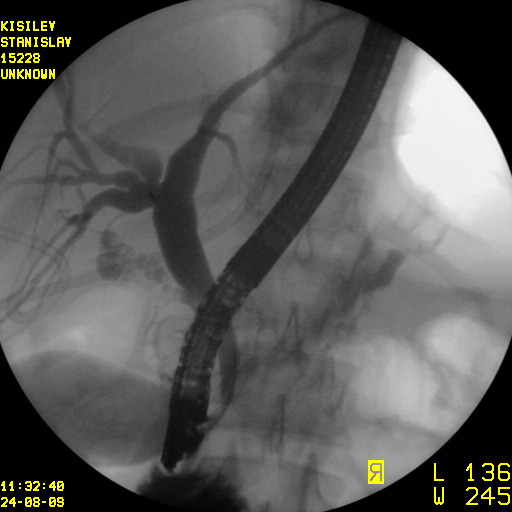

Минимально инвазивное лечение при эхинококковых кистах печени, осложнившихся прорывом в желчные протоки

Представлены клинические наблюдения редкого осложнения эхинококкоза печени – прорыва эхинококковой кисты в желчные протоки. Осложнение стало причиной обструкции желчных протоков, механической желтухи и холангита. Освещены этапы диагностики, роль УЗИ в выявлении осложнений эхинококкоза печени, рассмотрены способы минимально инвазивного лечения с применением эндоскопических и чрескожных технологий под контролем лучевых методов.